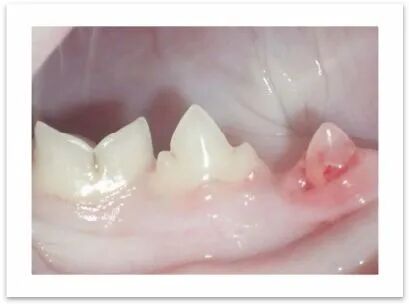

牙吸收病的症状

大多数病猫无临床症状,部分猫会出现流口水症状。

其它症状包括牙龈出血,牙龈增生或咀嚼困难等

一些猫在采食过程中会出现食物掉落的情况

(尤其是在采食较硬的食物时)

另外咀嚼时可能有嘶嘶声或动作异常

常见有炎症疼痛,骨髓炎,牙槽骨膨大,牙根硬化等

牙槽骨膨大